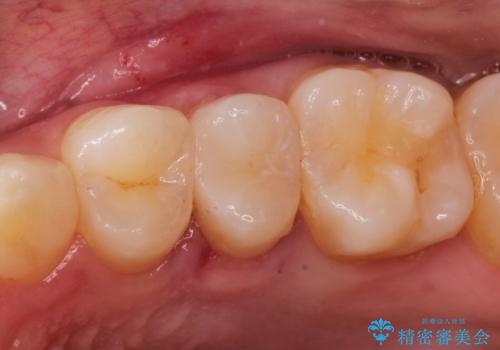

セラミッククラウン。虫歯の治療

- 定期検診にて不良補綴物、及び虫歯を認めオールセラミッククラウンにて治療を行いました。

右上第二小臼歯はカリエス除去中に露髄を認め、部分的断髄法にて歯髄を保存しております。